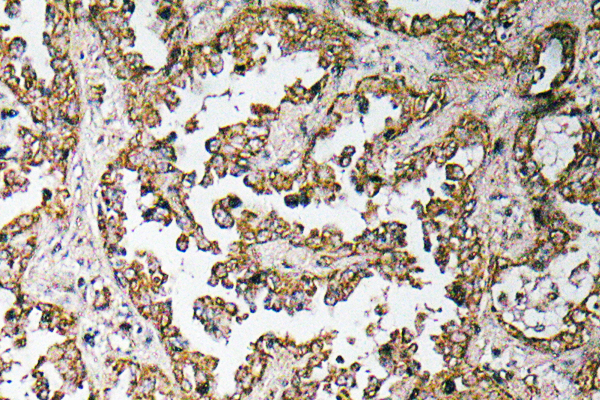

ApplicationsELISA, ImmunoHistoChemistry

Anti-HCFC1 AntibodyA98866

ApplicationsELISA, ImmunoHistoChemistry